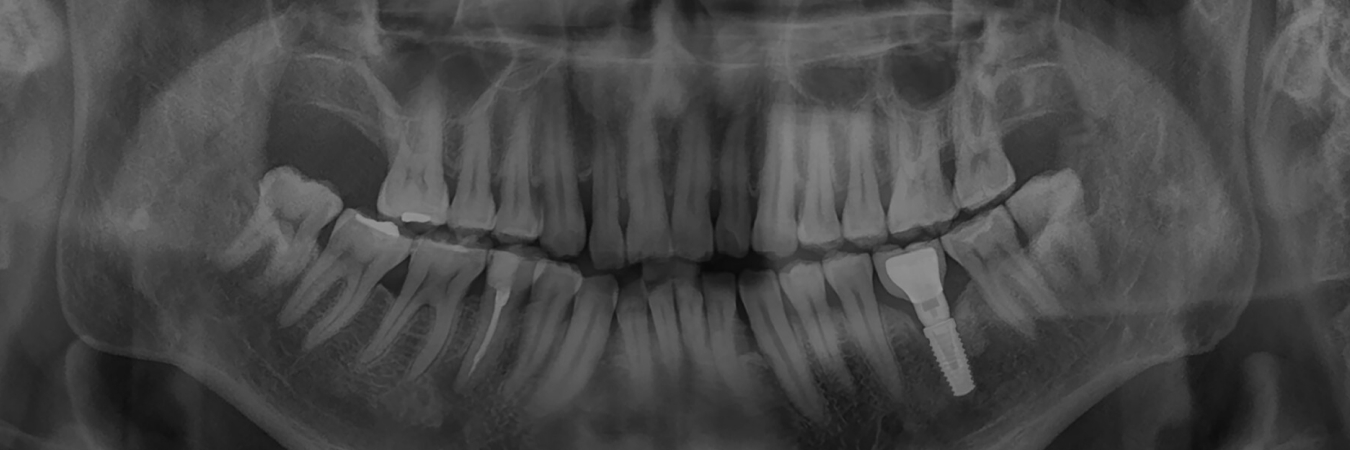

We begin by administering either a local or general anesthetic to numb the area or put you into a sleep-like state. We then make a small incision through the gums and insert the titanium implant post deep into the bone of the jaw. The implant site is given time to heal, and will naturally fuse with the bone in about six months. After this time, we’ll create new restorations for your smile that will attach to or snap onto the implant. Your implant can last for several decades without showing any signs of wear or damage.